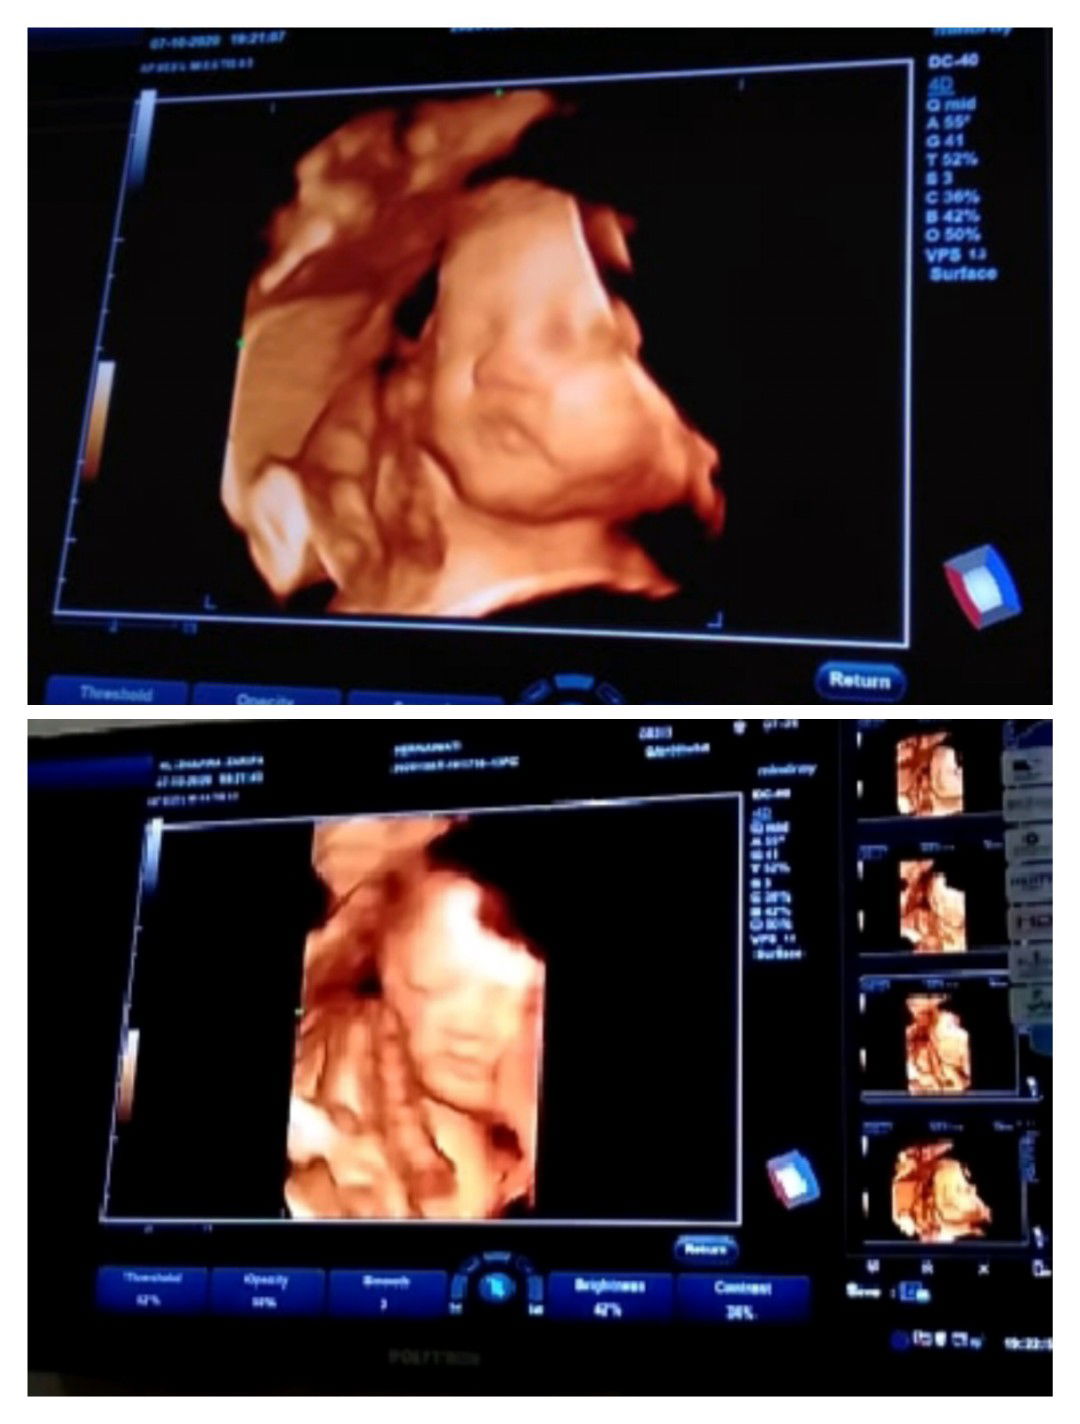

34 week masih sungsang,pdhl rajin jalan pagi ,senam,sujud juga tiap hari 😭 apa msh bisa muter y Bu

34 week masih sungsang

aku aja pas 34 sungsang bun,alhamdulillah pas 36 udah dibawah kepalanya. cuma banyakin sujud aja,jangan banyak jalan dulu kalau posisi sungsang kata dokter spog nya,takut yang masuk panggul bokong nya. benerin posisi detun dulu